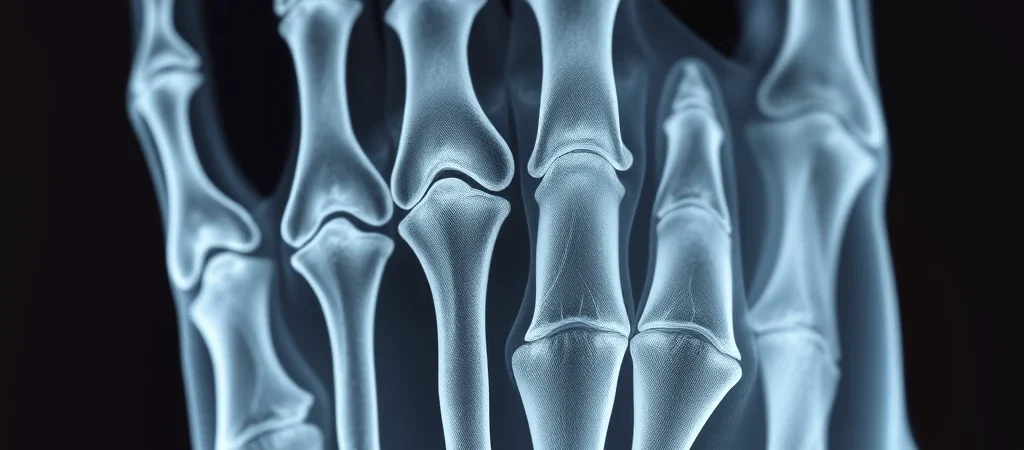

ಮುರಿದ ಮೂಳೆಗಳಿಗೆ ಹೊಸ ಸಂಶೋಧನೆ: ಕೇವಲ 3 ನಿಮಿಷದಲ್ಲಿ ಚಿಕಿತ್ಸೆ

ಬೀಜಿಂಗ್: ಚೀನಾದ ವಿಜ್ಞಾನಿಗಳು ಭಾನಿಯ ಮುರಿದ ಮೂಳೆಗಳನ್ನು ಕೇವಲ ೩ ನಿಮಿಷಗಳಲ್ಲಿ ಸಿದ್ಧಪಡಿಸುವ ವೈದ್ಯಕೀಯ ಅಂಟಕಾರಿ ವಸ್ತುವೊಂದನ್ನು ಅಭಿವೃದ್ಧಿಪಡಿಸಿದ್ದಾರೆ. ಈ ‘ಬೋನ್-೦೨’ ಎಂದು ಕರೆಯಲ್ಪಡುವ ಗ್ಲೂ, ಲೋಹದ ತೊಟ್ಟೆಗಳಂತಲ್ಲದೆ, ಎಲೆಯ ಸಹಜ ಪ್ರಕ್ರಿಯೆಯಲ್ಲಿ ದೇಹಕ್ಕೆ ಶೋಷಣೆಯಾಗಿ, ಎರಡನೇ ಶಸ್ತ್ರಚಿಕಿತ್ಸೆಯ ಅಗತ್ಯವನ್ನು ತೊಡೆದುಹಾಕುತ್ತದೆ.

ಝೆಜಿಯಾಂಗ್ ಪ್ರಾಂತದ ಸರ್ ರನ್ ರನ್ ಷಾ ಆಸ್ಪತ್ರೆಯ ಸಹಾಯಕ ಮುಖ್ಯ ಅಸ್ಥಿರೋಗ ಶಲ್ಯಚಿಕಿತ್ಸಕ ಲಿನ್ ಜಿಯಾನ್ಫೆಂಗ್ ನೇತೃತ್ವದಲ್ಲಿ ರೂಪಿಸಲ್ಪಟ್ಟ ಈ ಆವಿಷ್ಕಾರ, ನೀರಿನಡಿಯಲ್ಲಿ ಕಲ್ಲುಗಳಿಗೆ ಅಂಟಿಕೊಳ್ಳುವ ಕಾಕ್ಕದ ರೀತಿಯನ್ನು ಪ್ರೇರಣೆಯಾಗಿಟ್ಟುಕೊಂಡು ರಚಿಸಲಾಗಿದೆ. ಇದು ರಕ್ತಸಿಕ್ತ ಪರಿಸರದಲ್ಲಿ ಸಹಜವಾಗಿ ಅಂಟುಹೊಂದುತ್ತದೆ, ಇದರಿಂದ ಸಾಂಪ್ರದಾಯಿಕ ಅಂಟಕಾರಿಗಳ ಸಮಸ್ಯೆಗಳನ್ನು ನಿವಾರಿಸುತ್ತದೆ.

ಈ ಗ್ಲೂ, ೪೦೦ ಪೌಂಡ್ಗಿಂತ ಹೆಚ್ಚಿನ ಬಂಧನ ಶಕ್ತಿ, ೦.೫ ಎಂಪಿಎ ಇಂಟರ್ ಶಿಯರ್ ಸ್ಟ್ರೆಂಗ್ತ್ ಮತ್ತು ೧೦ ಎಂಪಿಎ ಕಂಪ್ರೆಸಿವ್ ಸ್ಟ್ರೆಂಗ್ತ್ ಅನ್ನು ಒದಗಿಸುತ್ತದೆ. ಸಾಂಪ್ರದಾಯಿಕ ಇಂಟರ್ ಲೋಹದ ತೊಟ್ಟೆಗಳು ಮತ್ತು ಸ್ಕ್ರೂಗಳೊಂದಿಗಿನ ಶಸ್ತ್ರಚಿಕಿತ್ಸೆಗಿಂತ ಇದು ೩ ನಿಮಿಷಗಳಲ್ಲಿ ಪೂರ್ಣಗೊಳ್ಳುತ್ತದೆ